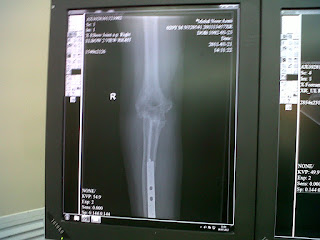

X- ray

Ni lah nak wut operation Right Thumb ORIF (open reduction internal fixation)

Die ader fracture kat Right Thumb P1